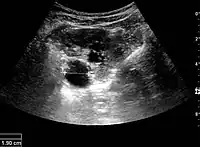

Figure 7. Advanced polycystic kidney disease with multiple cysts.[1]